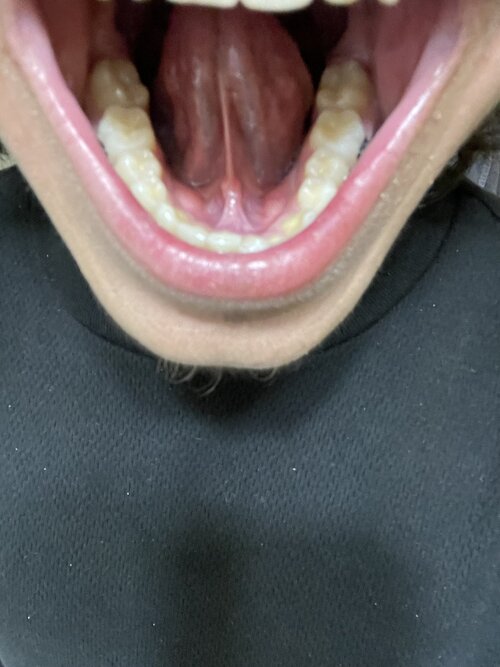

i have a bad deep bite with a fairly narrow plate i dont have any breathing issues or nothing tho im worrying about, because i dont want to get fucked over and have my maxilla pushed back any solutions? and if so will any of these solutions cause problems and or be a issue in the future?